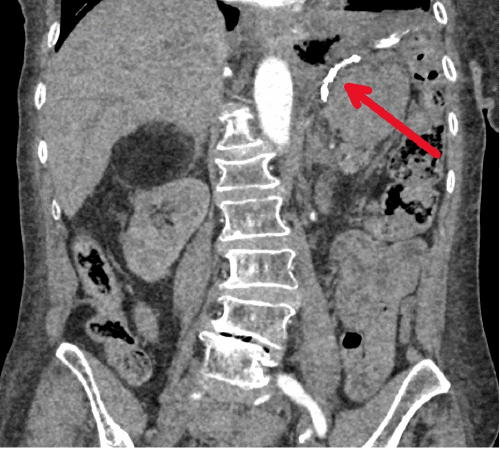

Within the next 24 hours of presentation, a CT scan with and without contrast was performed and was negative for any active gastrointestinal hemorrhage; however, post Roux-en-Y gastric bypass changes were visualized, and hyperdense impacted material was noted within the gastric remnant (Figure 1). Radiographically this was interpreted as possible gastritis of the remnant stomach.

Figure 1. Coronal CT Scan Revealing Hyperdense Material Located in Gastric Remnant. Published with Permission